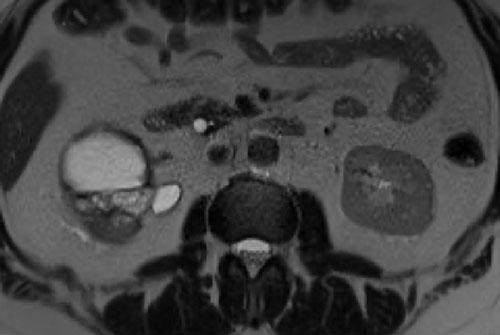

Các hình ảnh bao gồm: T2W mặt cắt ngang (axial), T1W mặt cắt coronal có kỹ thuật xóa mỡ (fatsat) và tiêm Gadolinium, và cuối cùng là T2W mặt cắt coronal.

Có một tổn thương dạng nang trong thận phải với nhiều vách ngăn mỏng (> 4 vách).

Các vách ngăn được thấy rõ hơn trên các hình ảnh mặt cắt ngang.

Các vách ngăn không có biểu hiện ngấm thuốc.

Theo phân loại cũ, tổn thương này sẽ được xếp vào nhóm IIF.

Trong phân loại cập nhật năm 2019, các vách ngăn không ngấm thuốc không được tính là vách ngăn thực sự, do đó tổn thương được hạ bậc xuống nang Bosniak II.

Nang này trước đây đã từng xuất huyết và không cho thấy bất kỳ thay đổi nào trong quá trình theo dõi suốt 5 năm.